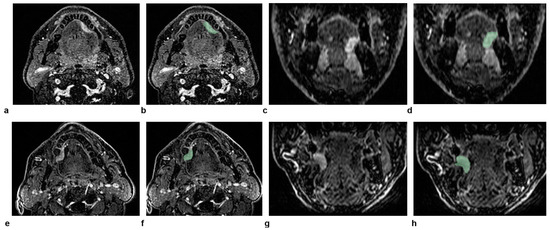

3.2. Illustrative Cases

Two representative patients with the same radiological staging (cT2N0) but different clinical outcomes are illustrated in Figure 4. The radiomic-only model and all of the combined models provided the correct predictions for both patients. This can be explained considering that the values of large-area high-gray-level emphasis, large-dependence high-gray-level emphasis, and long-run emphasis were all lower in the patient without recurrence compared to the patient with recurrence (6.6 × 104, 4.7 × 103, and 1.1 versus 1.0 × 105, 1.5 × 104, and 1.2, respectively).

Figure 4. The figure shows dynamic high-spatial-resolution T1-weighted images after contrast medium administration in the axial and coronal planes of two patients with the same radiological staging (cT2N0) but different clinical outcomes, for whom the radiomic-only model and all combined models provided the correct predictions. In the top row (ad), the images represent a 58-year-old male patient who did not experience a recurrence, with the corresponding delineated lesion outlined in green on the same planes (b,d). In the bottom row (eh), the images represent a 71-year-old male patient with a recurrence. Similarly, the axial and coronal images (e,g) show the lesion after contrast medium administration, with the delineated lesion outlined in green (f,h).